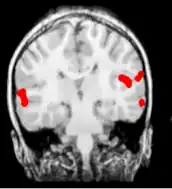

![]() | |

| Child with symptomatic epileptic spasms of right hemisphere origin | |